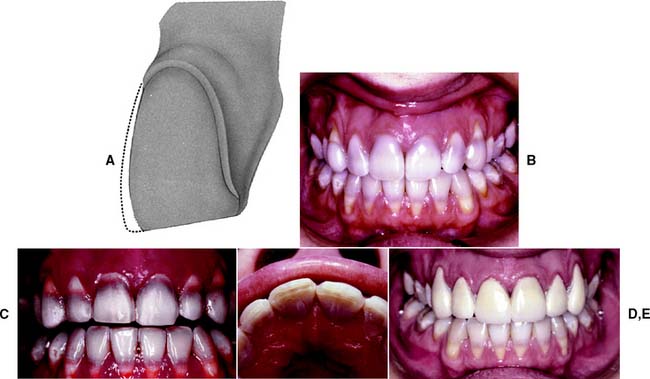

Laminate veneering (Fig. 11-11) is a conservative method of restoring the appearance of discolored, pitted, or fractured anterior teeth. It consists of bonding thin ceramic laminates onto the labial surfaces of affected teeth. The bonding procedure is the same as that for ceramic inlays except that a photopolymerize luting resin is usually used.

Fig. 11-11 Esthetic facial veneers. A and B, Unesthetic maxillary incisors with crowding. The 50-year-old patient was not prepared to pursue an orthodontic option. C, Diagnostic waxing to optimal incisor form. D, Vacuum-formed matrix used to place interim restoration resin directly on the unprepared teeth to simulate the final esthetics. E, Tooth preparations. F, Restorations in place.

The main advantage of laminate veneers is that they are conservative of tooth structure. Typically, only about 0.5 mm of facial reduction is needed. Because this is confined to the enamel layer, local anesthesia is not usually required. The main disadvantage of the procedure relates to difficulty in obtaining restorations that are not excessively contoured. This is almost inevitable in the gingival area if enamel is left for bonding. Little has been reported about the effect of the restorations on long-term gingival health and whether or how often they need replacement over a patient’s lifetime.

Esthetic veneers should always be considered as a conservative alternative to cemented crowns. In many practices, they have largely replaced metal-ceramic crowns for the treatment of multiple discolored but otherwise sound teeth.

The gingival third and proximal line angles are often overcontoured with these restorations (Fig. 11-12). Therefore, maximum reduction should be achieved with minimum penetration into the dentin.